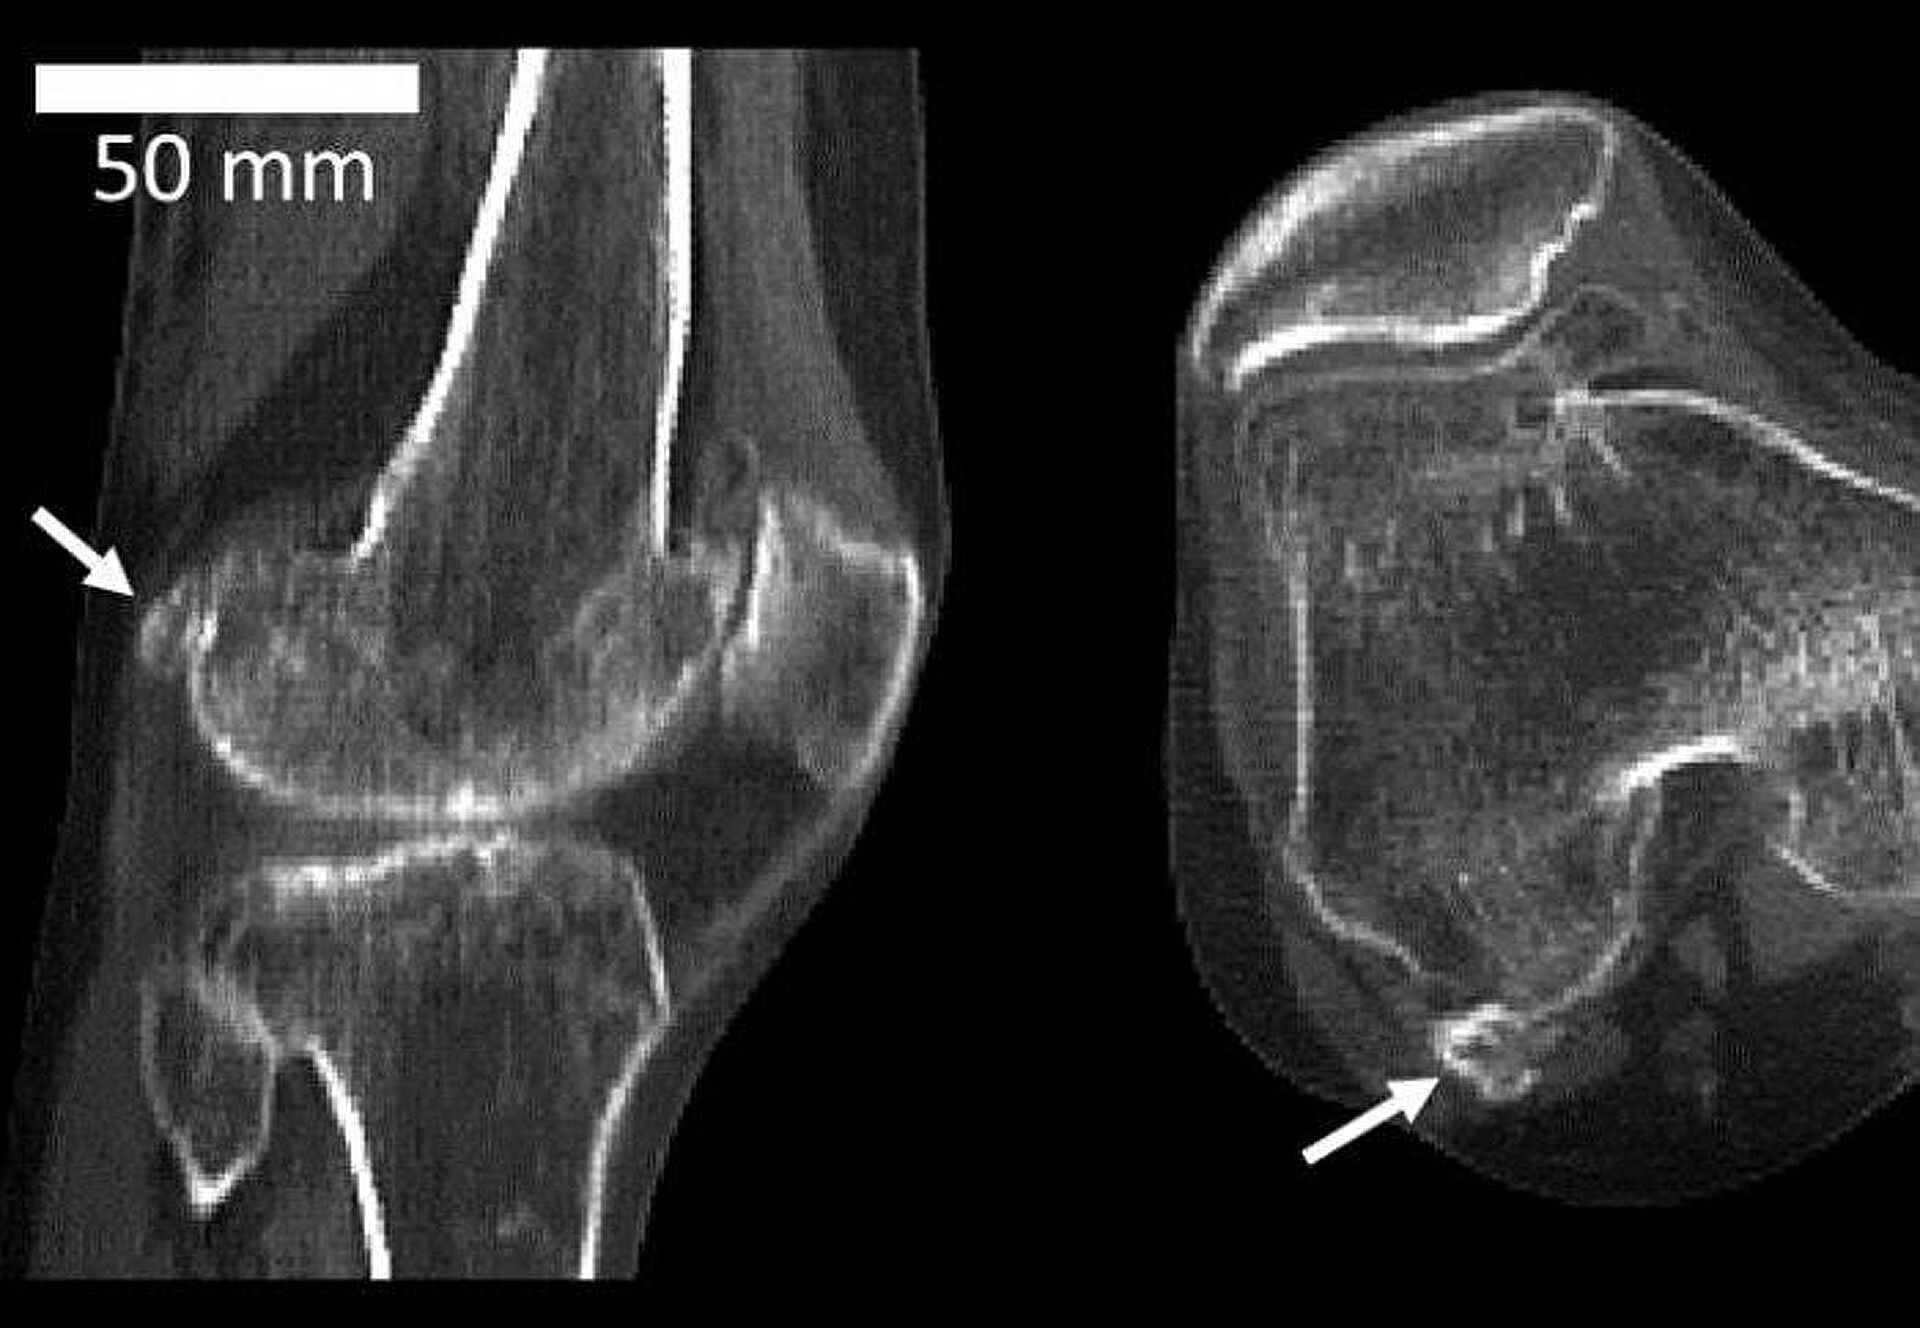

За последние 150 лет медики почти в три с половиной раза чаще наблюдают у пациентов фабеллу — маленькую косточку, которая прикрывает коленный сустав сзади. Она сильно мешала нашим предкам — снижала маневренность и гибкость сустава, поэтому встречалась очень редко.

Теперь же, как полагают специалисты, коленной чашечке понадобилась дополнительная защита: средний рост и вес людей увеличились, нагрузка возросла, и эта косточка необходима.Cовременный человек в среднем питается лучше, чем те, кто жил 100-150 лет назад. Люди сейчас выше и тяжелее — это спровоцировало развитие более длинных голеней и крупных икроножных мышц, что, в свою очередь, усилило давление на колено.

Фабелла — маленькая косточка, которая прикрывает коленный сустав сзади. За последние 150 лет она стала чаще встречаться у людейК такому выводу пришли исследователи из Имперского колледжа Лондона (Великобритания), проанализировав более 21 тысячи случаев фабеллы у жителей 27 стран. Как оказалось, если в начале прошлого века косточка встречалась примерно у 11,2 процента населения, то к 2018 году — уже у 39.

По мнению ученых, если тренд сохранится, то уже через сто лет фабелла будет у большинства людей на планете.